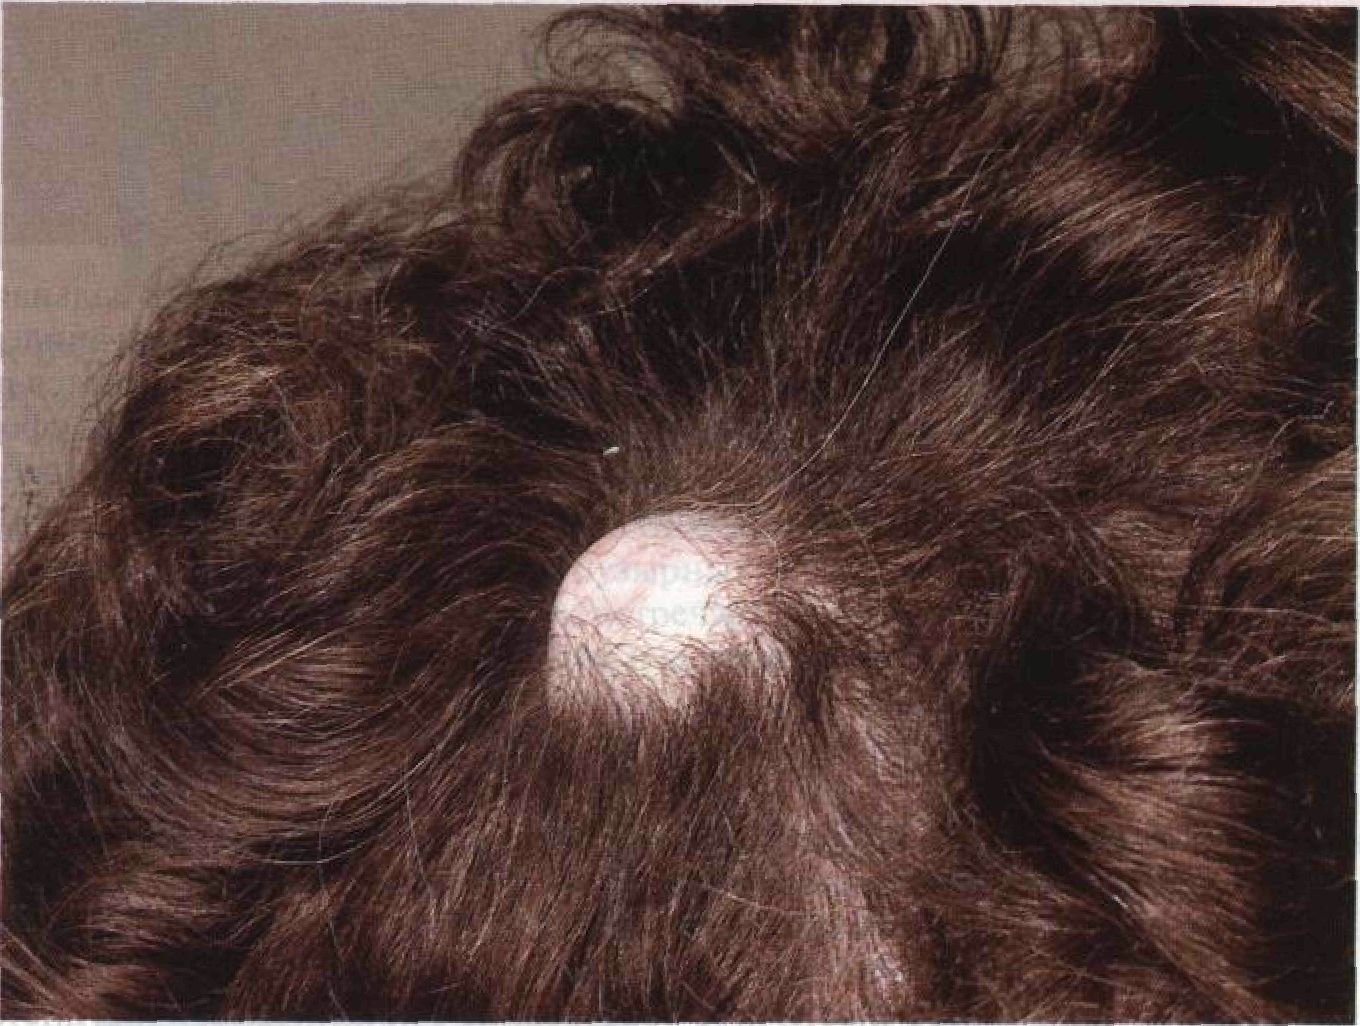

Фото раковой шишки на теле

Раковые шишки могут возникать не только на лице, но и на других частях тела. На фотографиях вы можете увидеть примеры раковых шишек на шее, руках, ногах и туловище. Обратите внимание на различные формы и размеры раковых шишек, а также на их внешний вид.